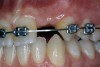

Periapical radiographs were taken to help determine the mesial-distal inclinations of the adjacent tooth roots (Figure 1). The radiographs revealed a serious issue, convergent roots for the right canine and right central, which eliminated that area as a potential implant-receptor site. The space between the left central and canine teeth was minimal, although the roots were relatively parallel. Clinical examination (manual palpation of the root eminences superiorly to the vestibule on the right side) confirmed the root convergence (Figure 2A). The flat, wide zone of the keratinized tissue and lack of interdental papilla was evident for the missing right lateral incisor. There was a marked difference in clinical appearance for the left lateral, which could impact the eventual plan of treatment (Figure 2B). Other significant clinical findings included bilateral facial bone concavities, which existed as a result of the congenitally missing tooth roots. As a diagnostic cue to the underlying bone topography, it is important to follow the demarcation between attached and unattached gingival tissue, and note the crestal width of the available keratinized tissue (Figure 2C).

Figure 2b  Pretreatment buccal views showed (A) root convergence, (B) a difference in clinical appearance of the left lateral, and (C) significant crestal width of keratinized tissue.

Figure 2b

Figure 2c  Pretreatment buccal views showed (A) root convergence, (B) a difference in clinical appearance of the left lateral, and (C) significant crestal width of keratinized tissue.

Figure 2c